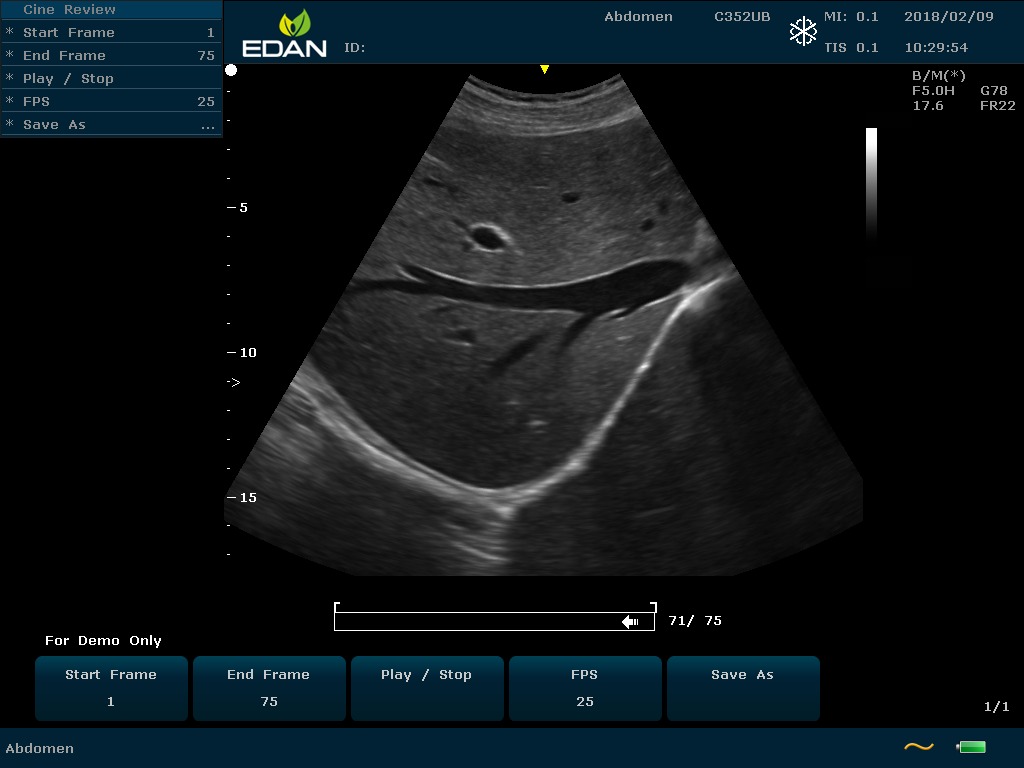

Особенность U60 Edan — расширенное применение. Ультразвуковой аппарат рекомендован для абдоминальных исследований, гинекологии и акушерства, кардиологии, педиатрии, урологии, изучения малых органов, сосудов. Для U60 Edan используются конвексные, линейные, фазированные и внутриполостные датчики.

Передовые технологии позволяют повысить качество визуализации в несколько раз. УЗИ-аппарат U60 Edan отличается возможностью быстрой настройки визуализации. Специальные функции позволяют моментально отображать данные за счет быстрой оптимизации параметров. Режимы визуализации: B-mode, M-mode, Color Doppler, Power Doppler Imaging, Pulsed Wave Doppler, Continuous Doppler.

Данная модель является совершенным этапом эволюции своих предшественников, отличается улучшенной эргономикой, современным оптимизированным дизайном, возможностями четкой и высокоэффективной визуализации органов.